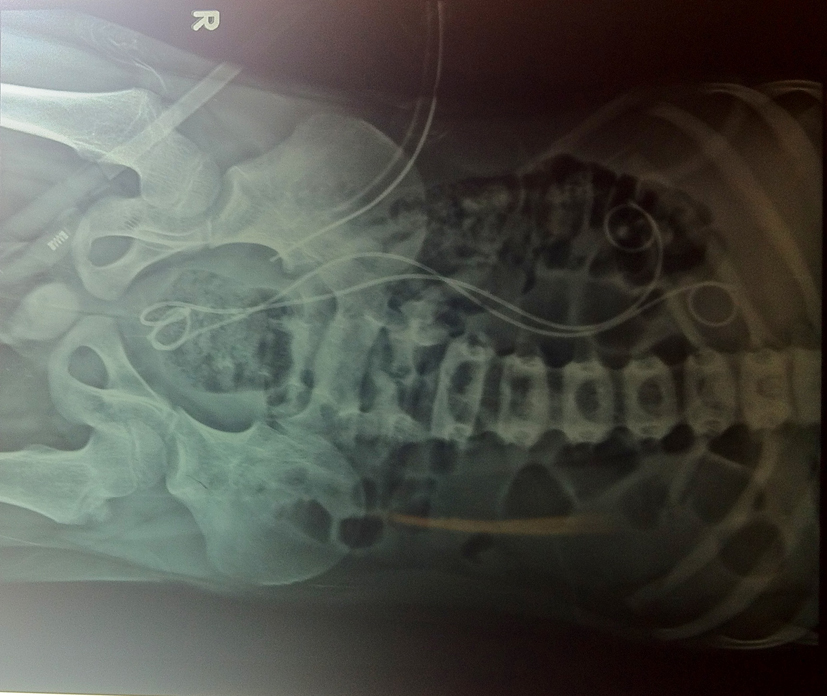

A 7-year-old boy presented with dull pain in right flank with repeated episodes of urinary tract infection. Clinically, no abnormality was detected. Ultrasonography revealed right gross hydronephrosis with hydroureter up to ureterovesical junction. Micturating cystourethrogram suggested grade V reflux in both ureters of complete duplication (Fig. 1). Right kidney had 20% split function (glomerular filtration rate: 18 mL/min). Cystoscopy revealed both the ureteric orifice in small prostatic urethral diverticulum (Fig. 2). Common sheath ureteric reimplantation was done by Politano-Leadbetter technique with double J stenting (Fig. 3, 4).

![]() Click for large image | Figure 4. Post-operative X-ray. |